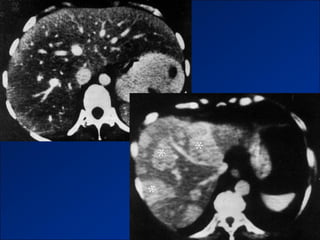

Figure 2a. Large regenerative nodules in a 34-year-old woman with subacute (25 days) Budd-Chiari

syndrome due to factor V Leiden deficiency.

©2002 by Radiological Society of North America   Brancatelli G et al. Radiographics 2002;22:847-862

Figure 3a. Large regenerative nodules in a 31-year-old woman with Budd-Chiari syndrome of

unknown origin.

©2002 by Radiological Society of North America

Brancatelli G et al. Radiographics 2002;22:847-862

Hình ảnh trên CLVT

- Teo gan ở ngoại vi.

- Phì đại thùy gan trung tâm - phân thùy đuôi.

- Tuần hoàn bàng hệ qua hệ cửa.

- Huyết khối TM cửa – TM dẫn lưu.

- Các shunt mạch máu trong gan.